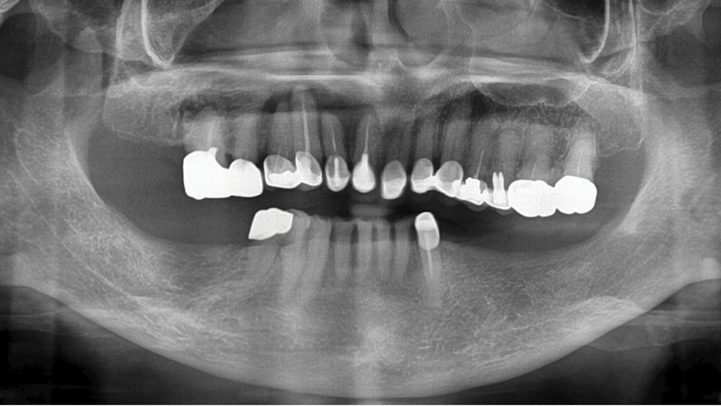

Clinical case: # 46 implant placement & GBR using i-Gen membrane for significant vertical resorption & mixed bone defect

- Courtesy of Dr. Iulian Filipov, Romania -

Keywords

AnyRidge, mandibular posterior, i-Gen, resorption, bone defect, bone regeneration, space management, #46, GBR, Dr. Iulian Filipov

Products:

AnyRidge implant system, i-Gen